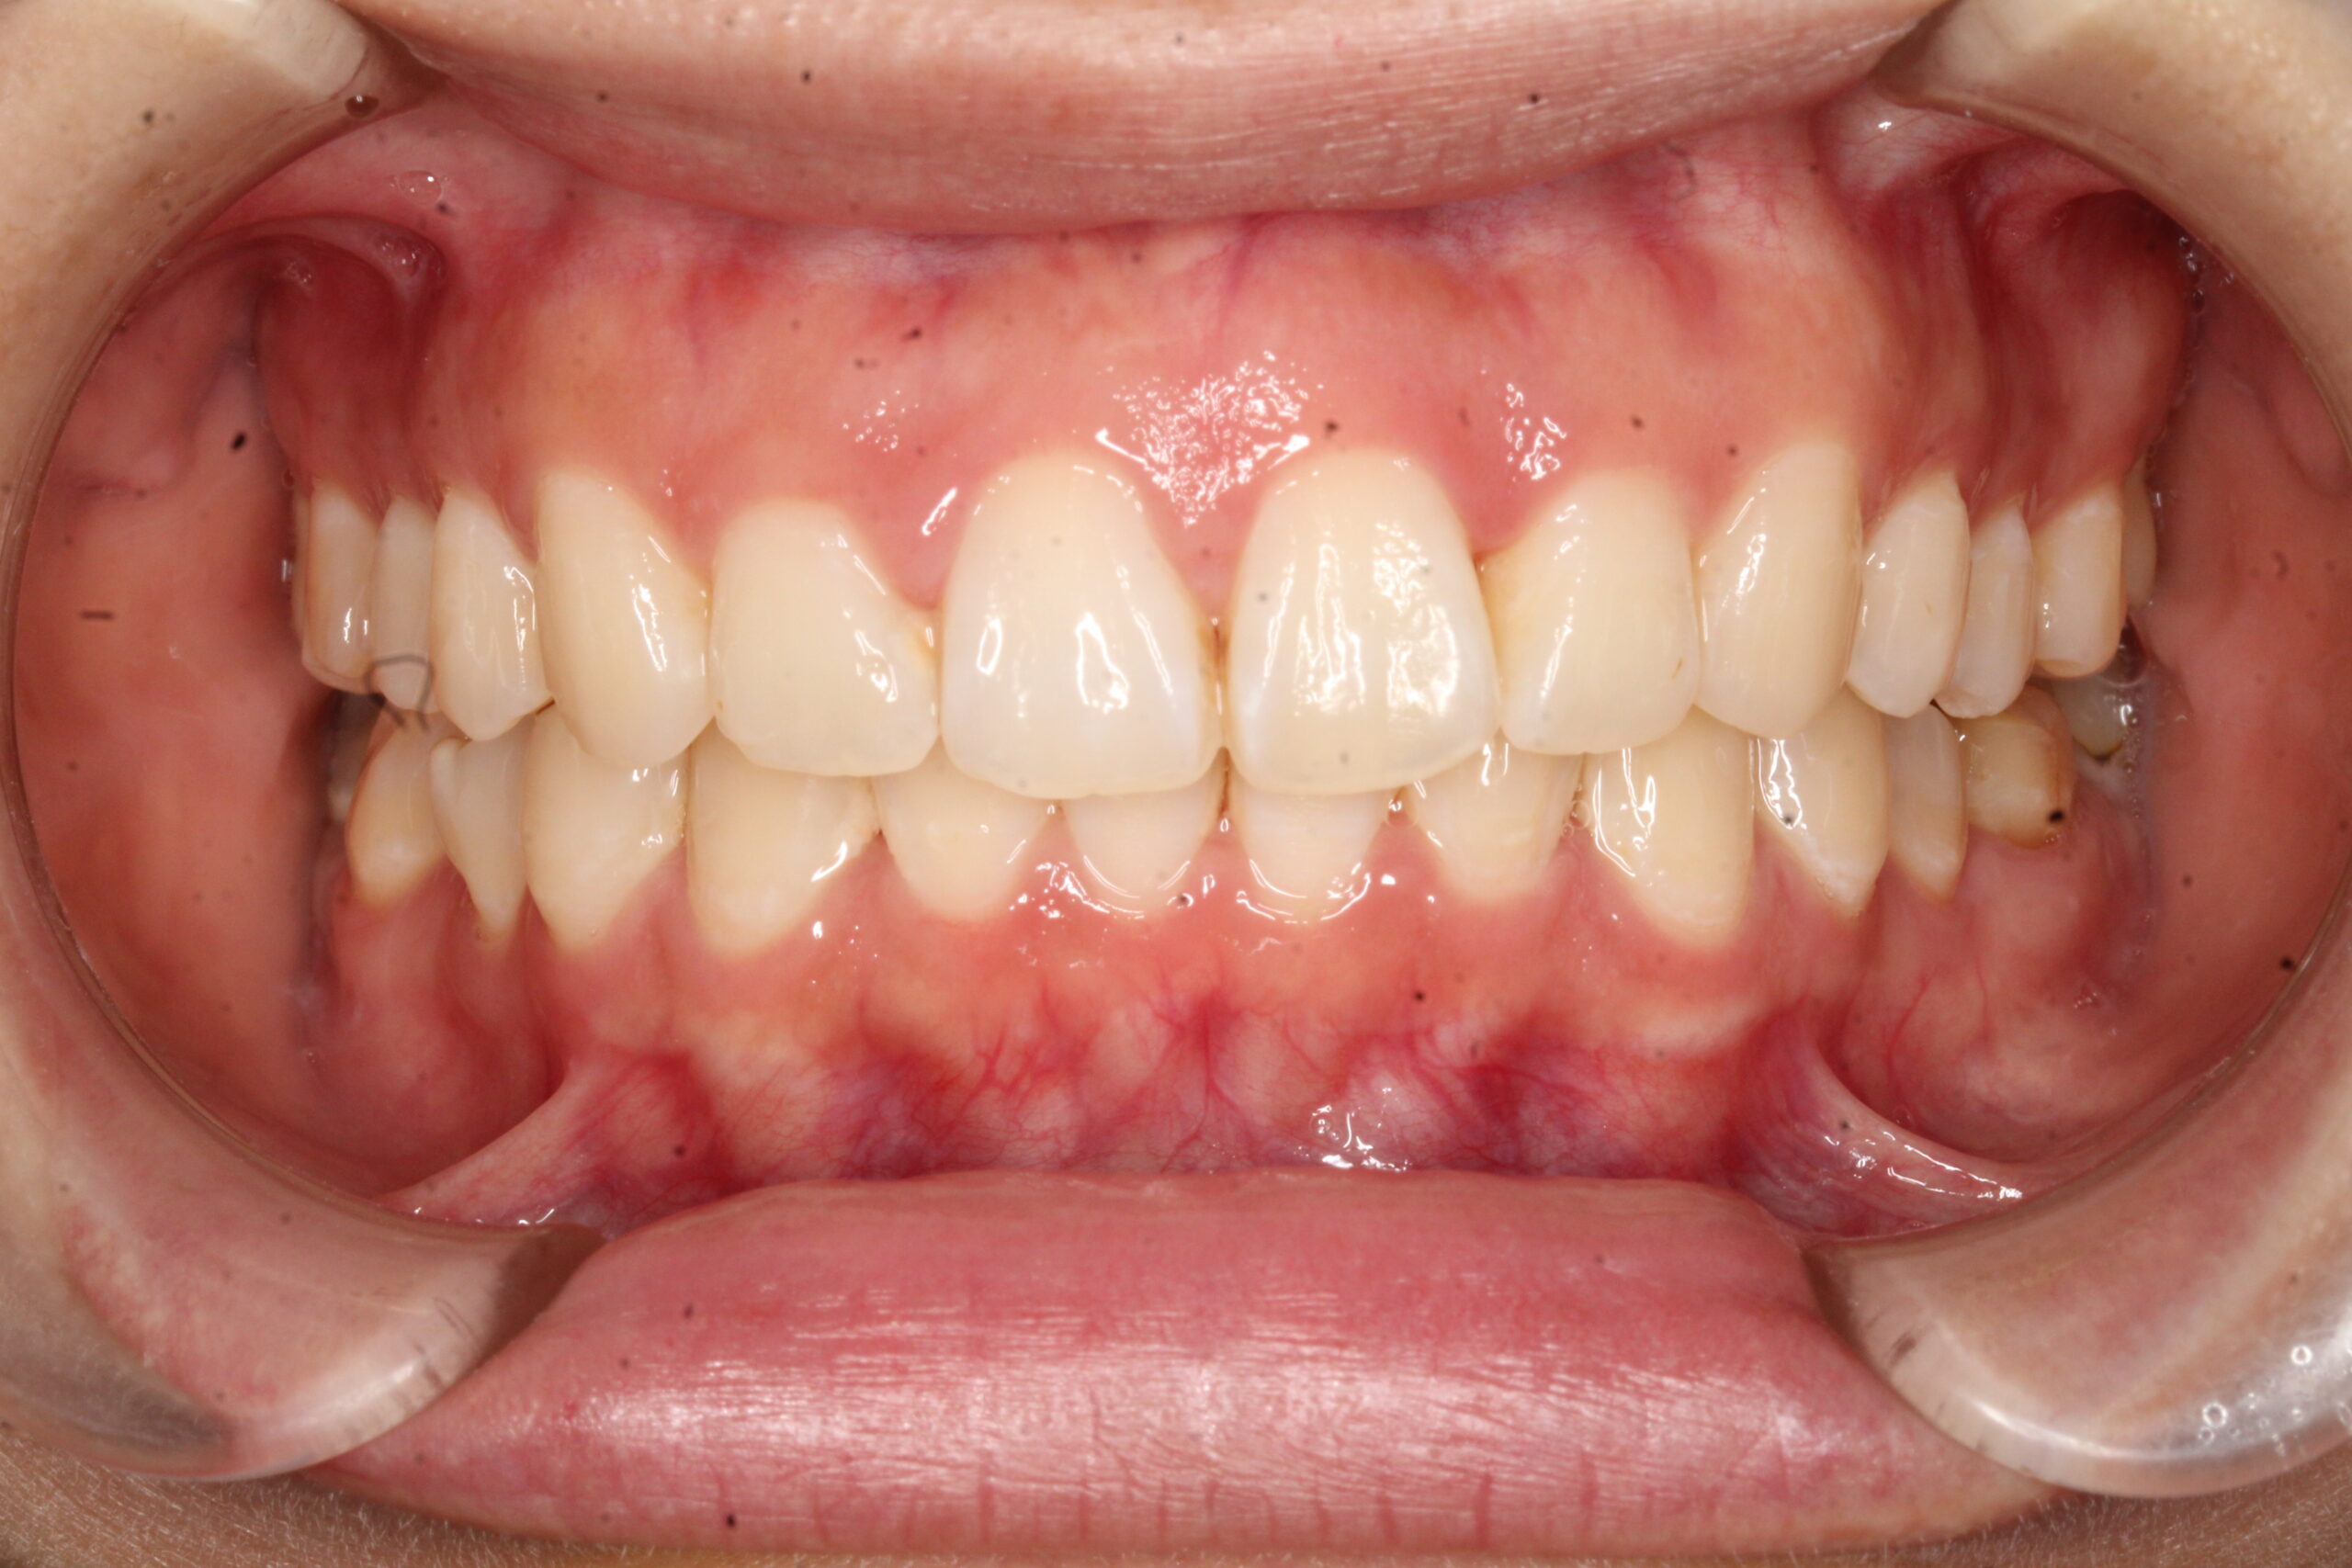

矯正術前:正面

矯正術後:正面